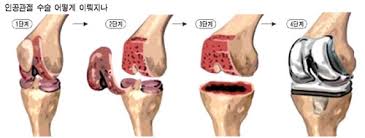

- 로봇 사용 여부, 수술방식(부분 vs 전치환), 병원급(대학병원·종합병원 등)에 따라 가격 차이가 큽니다.

- 로봇수술은 정확도 향상으로 관절 정렬, 인대 손상 최소화 등 기능 회복이 빠르고 통증 감소 효과가 있지만, 장기 생존율 차이는 크지 않다는 연구가 있습니다.

- 보험 수술도 충분히 표준 치료로 효과적이지만, 수술 후 관리와 재활이 더 중요합니다.